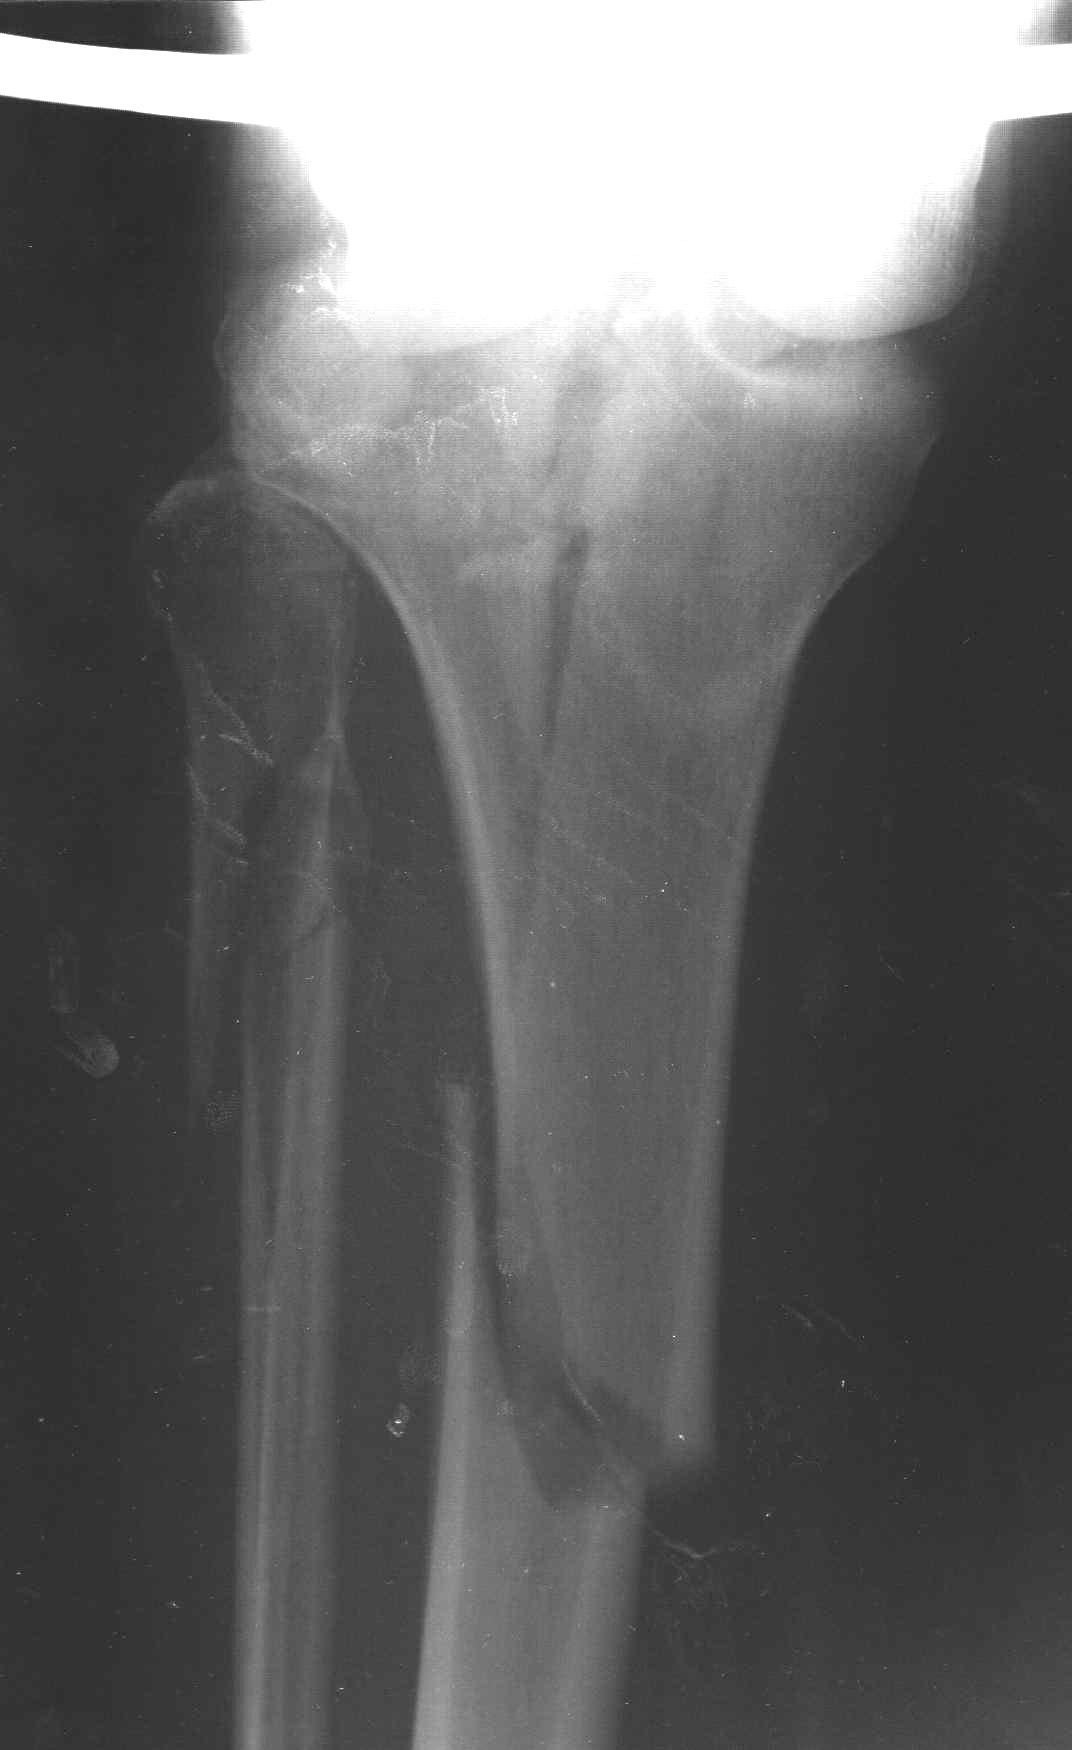

Пациенту сделали КТ - ухитрились сделать на шине Белера (не давал положить прямую ногу) - срезали передний отдел. Планируется на пятницу (24.12) на операцию - синтез  длинной мыщелковой LCP-пластиной Synthes :). Отек ближе к слову умеренный (окружность голени +4 см по сравнению со здоровой). КТ и снимок на вытяжении прилагаются.